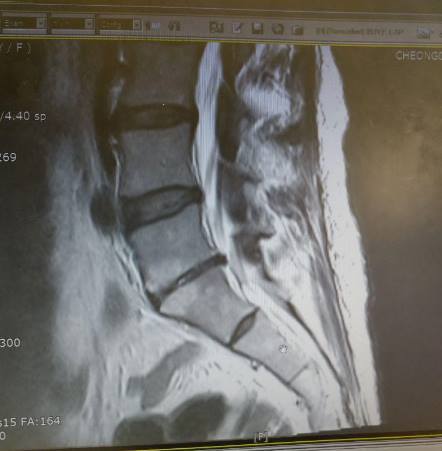

이상호 기자 페이스북(요추 추간판 퇴행 협착증 잘 아시는 분들 봐주세요).jpg